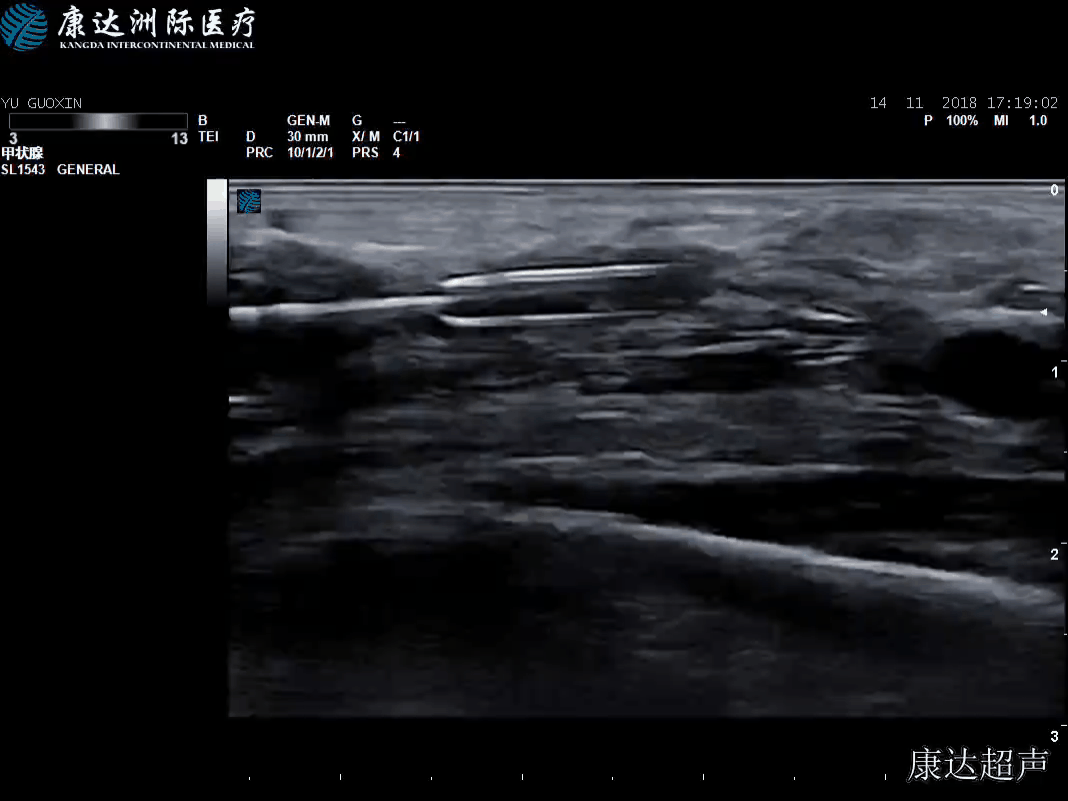

上臂头静脉逆行穿刺置入鞘管

引入超滑导丝,导丝顺利过吻合口放置在桡动脉

手术经过患者仰卧位,右前臂取外展位,消毒、铺巾。B超探头套上无菌膜,建立PT路径,在内瘘血管的近心端,距离肘部约2cm处为穿刺点,局麻后穿刺血管,成功后送入导丝,延超滑导丝进入6mmX40mm球囊,定位与血栓出加压球囊至25Pa,机械碎栓,撤压后重复加压1到2次,依次更换球囊位置至各个病变血管的数个狭窄段,分别加压、扩张后,回撤球囊,彩超探查内瘘血管通畅,血流量充足。顺序撤导管、撤鞘管,穿刺部位加压包扎。